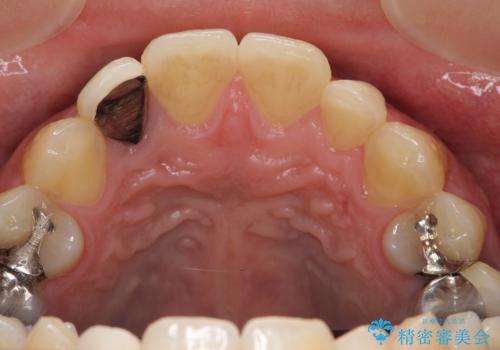

- 金属を使っていない被せ物に替えたいといらっしゃった方の症例です。

再根管治療終了後、オールセラミッククラウンによる補綴を行いました。